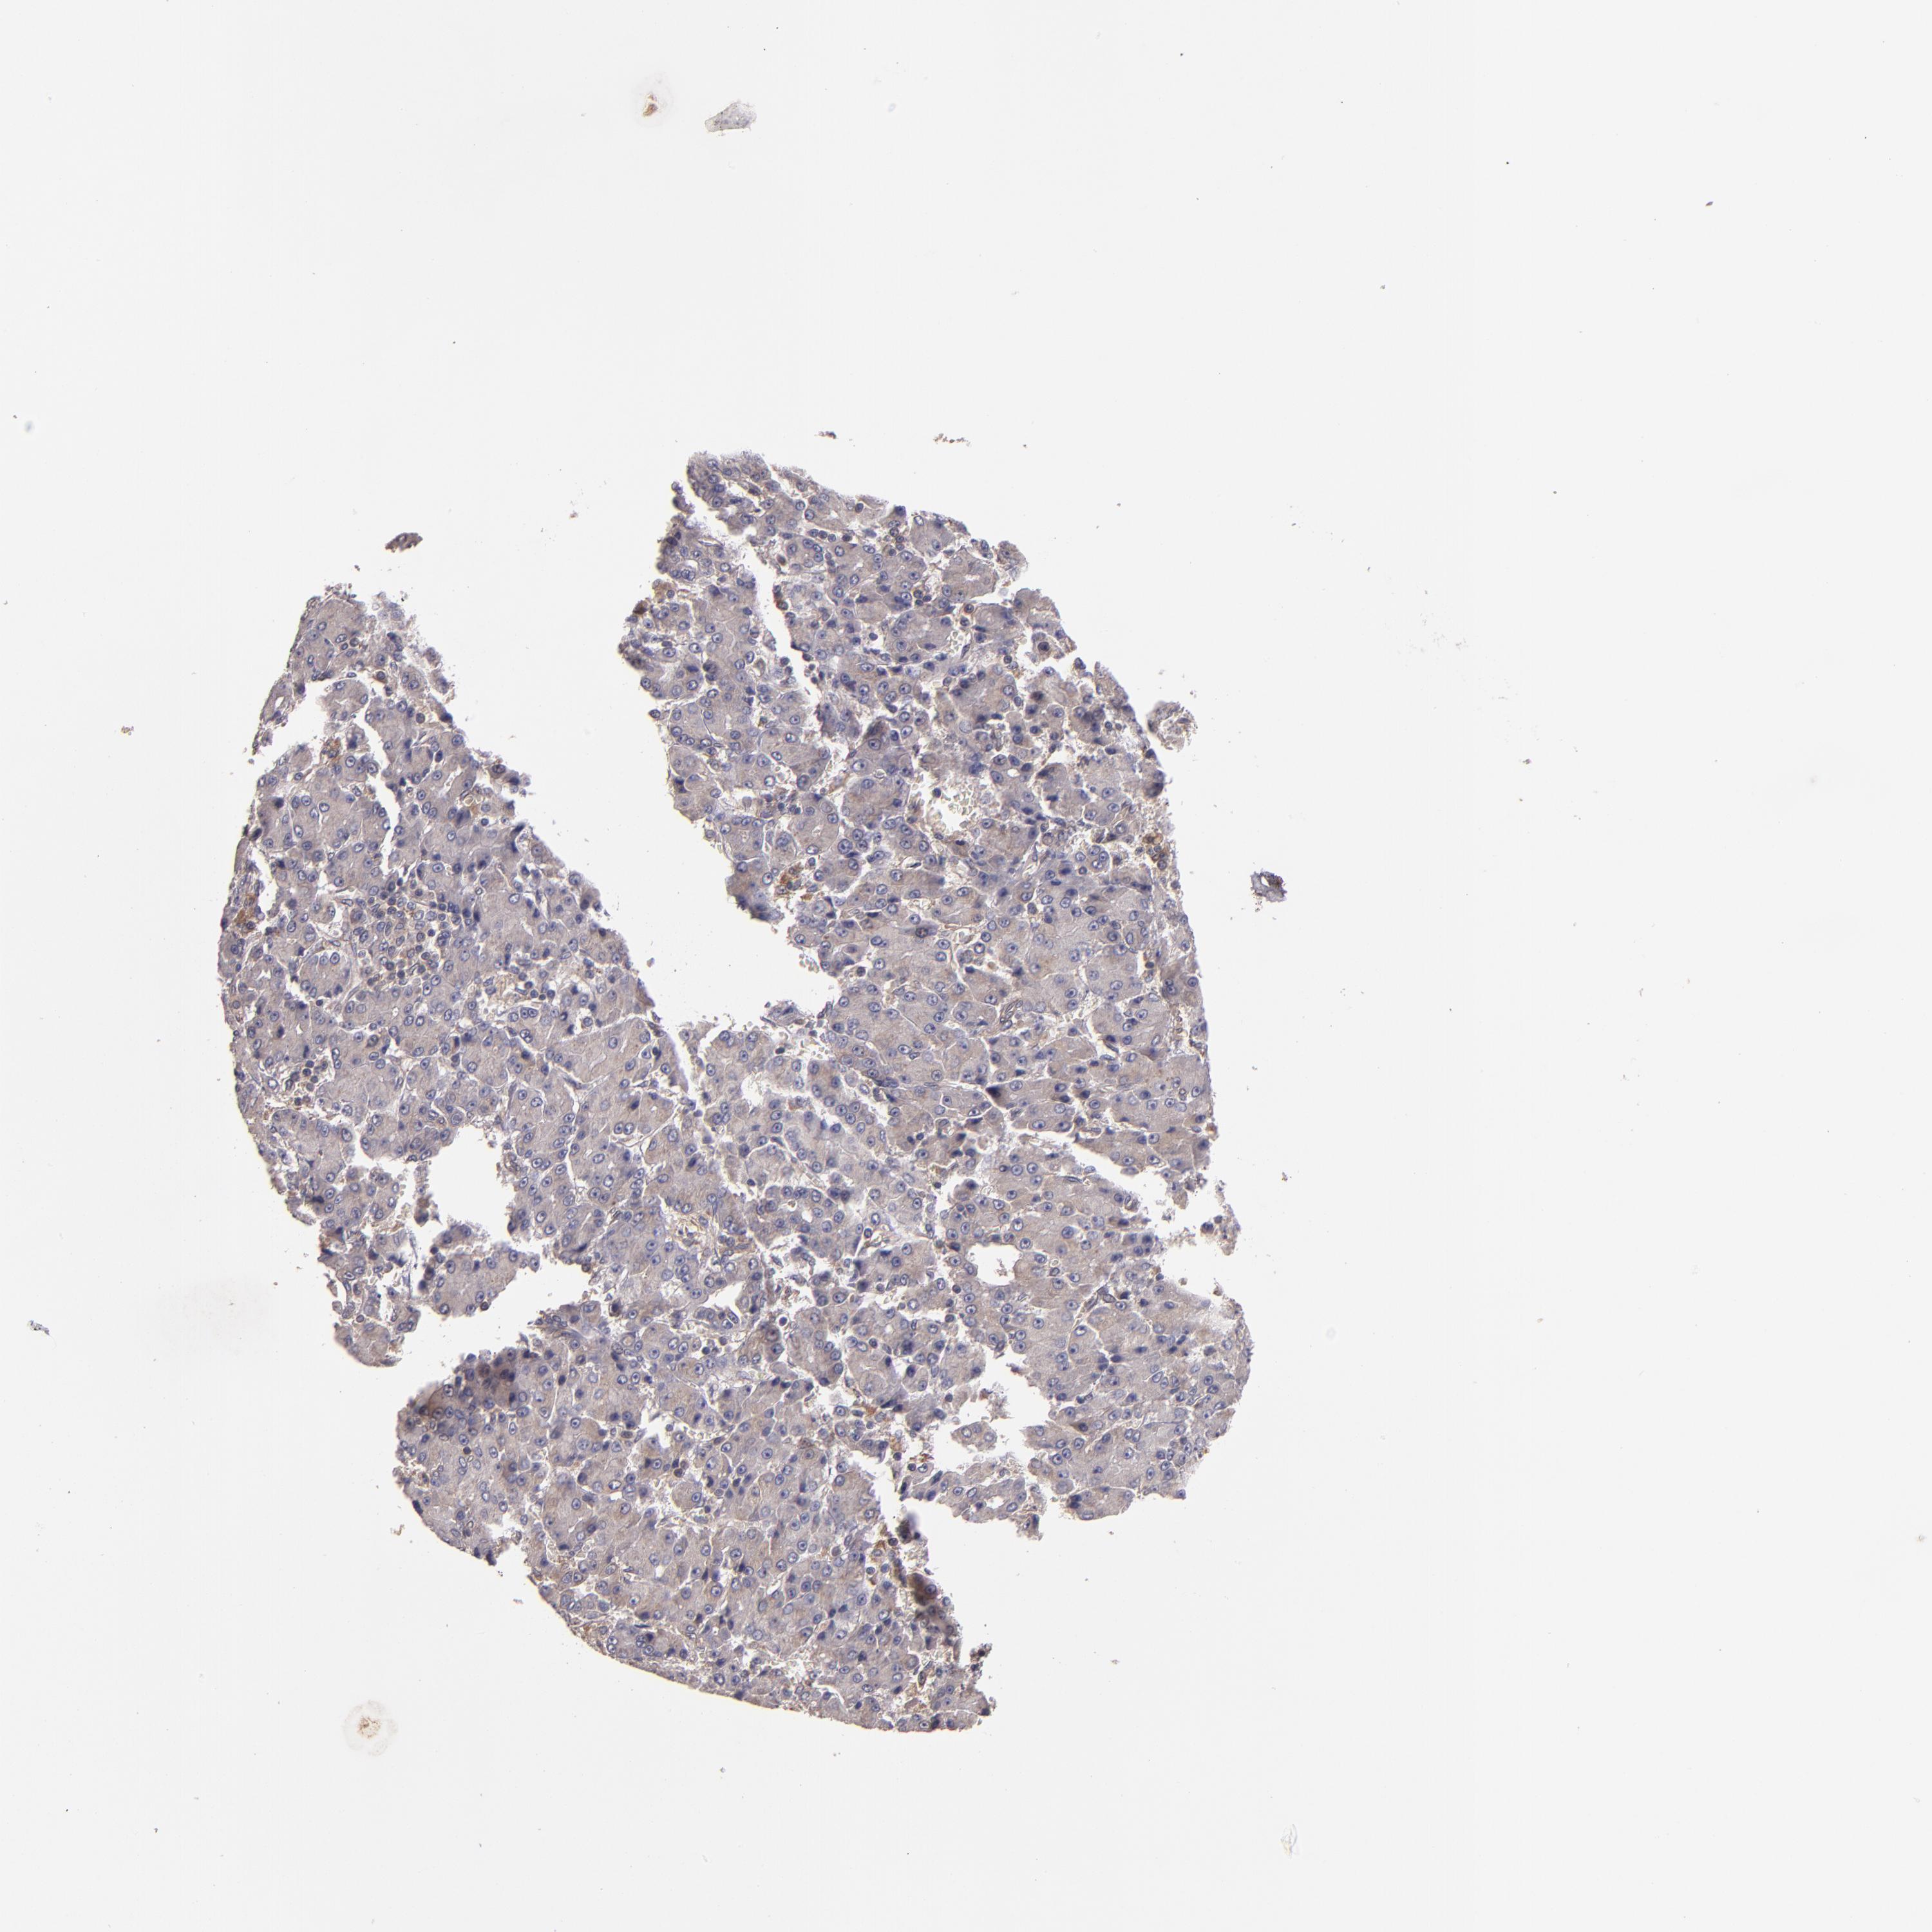

LIVER CANCER - Protein expressioni

A mouse-over function shows sample information and annotation data. Click on an image to view it in a full screen mode. Samples can be filtered based on level of antibody staining by selecting one or several of the following categories: high, medium, low and not detected. The assay and annotation is described here.

Note that samples used for immunohistochemistry by the Human Protein Atlas do not correspond to samples in the TCGA dataset.

Antibody stainingi

Antibody staining in the annotated cell types in the current human tissue is reported as not detected, low, medium, or high, based on conventional immunohistochemistry profiling in selected tissues. This score is based on the combination of the staining intensity and fraction of stained cells.

Each image is clickable and will lead to virtual microscopy that enables deeper exploration of all samples and also displays staining intensity scores, fraction scores and subcellular localization as well as patient and tissue information for each sample.

Antibody HPA002859

Antibody CAB011655

Staining

High

Medium

Low

Not detected

Intensity

Strong

Moderate

Weak

Negative

Quantity

>75%

75%-25%

<25%

None

Location

Nuclear

Cytoplasmic/membranous

Cytoplasmic/membranous,nuclear

Carcinoma, Hepatocellular, NOS

Cholangiocarcinoma